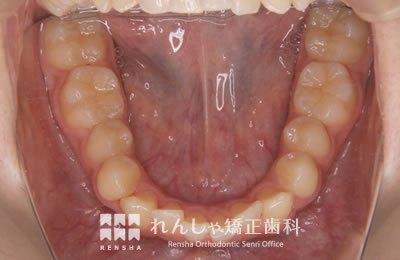

成人

歯列のサイズや形態を大きく変更することができませんが、歯列が極端に狭くなっている場合や、奥歯が前方に移動し前歯ががたついているケースでは、歯列の拡大や奥歯の後方移動を行うことで永久歯を抜歯せずにがたつきを改善できることがあります。このような場合はアライナー型(カスタムメイド)矯正(歯科)装置も治療の選択肢として有効です。

| 主訴 | 前歯のがたつき |

|---|---|

| 診断名 | Angle Class I 叢生 |

| 初診時年齢 | 18歳8か月 |

| 装置名 | マウスピース型カスタムメイド矯正歯科装置(製品名インビザライン・完成物薬機法対象外) |

| 抜歯非抜歯 | 非抜歯 |

| 治療期間 | 1年2か月 |

| 費用の目安 | 約55万円+消費税(検査料金、都度の処置費用等も合わせた総額) |

| リスク副作用 | 歯の移動に伴う軽微な歯根吸収、歯槽骨吸収、歯肉退縮(いずれも本症例ではほぼ無し)、矯正器具装着中のカリエスリスク増大(本症例ではカリエス発生無し) |